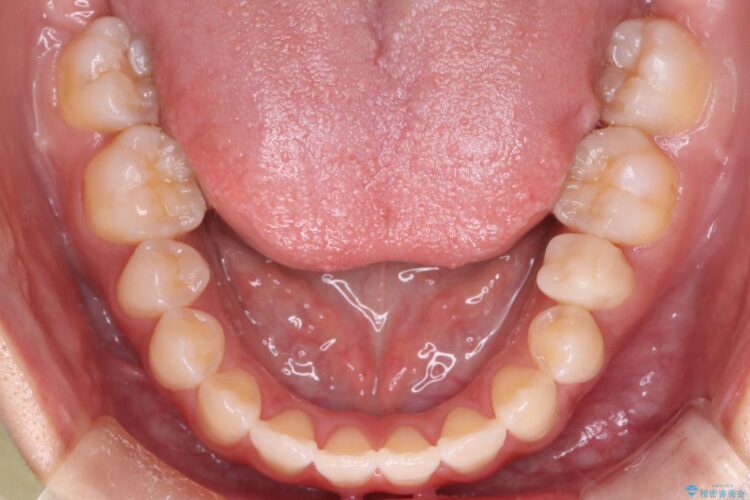

八重歯とガタつきが気になるとご来院された患者様です。

精密検査の結果、抜歯はせずIPR(歯と歯の間を削る処置)を行い、目立ちにくい審美ワイヤー装置にて歯列拡大を行うことで歯列を整える治療計画を立てました。